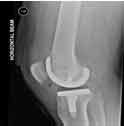

Robotic painless knee replacement surgery is a minimally invasive surgical procedure that uses advanced robotic technology to replace the damaged or arthritic knee joint with an artificial one. This innovative technique allows for greater accuracy and precision, resulting in less tissue damage and trauma to the surrounding area.

Total Knee Replacement Surgery, also known as Total Knee Arthroplasty, is a surgical procedure where the damaged or arthritic joint surfaces of the knee are replaced with artificial components made of metal and plastic. The goal of the surgery is to alleviate pain, improve mobility, and enhance the overall quality of life.